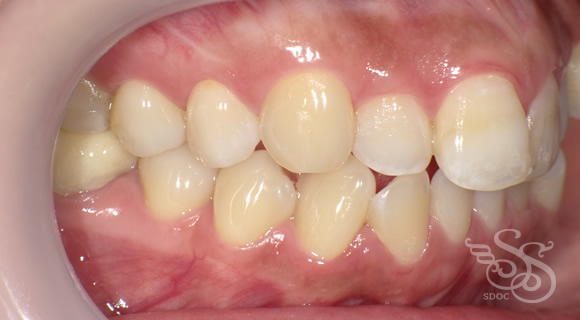

右側:術前

右側:術後